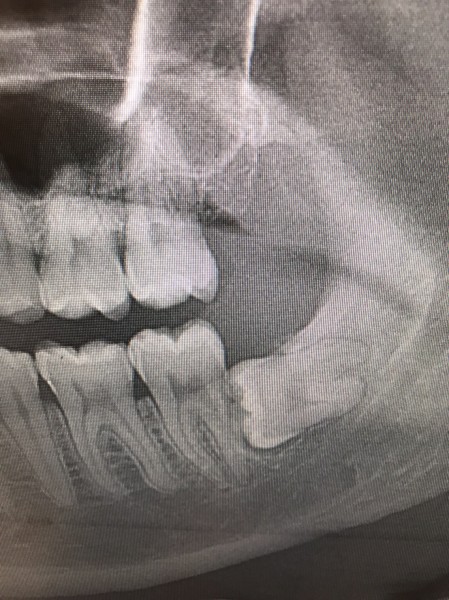

Case001 – 精密根管治療

精密根管治療のBefore/After

【Before】

CTで確認すると、膿んでしまっており骨が溶けてしまっている状態です。

骨がほとんどなく、歯が歯茎に刺さっているだけの状態でした。

当然、前医では抜歯という判定でした。

【After】

セカンドオピニオンで当院を受診。

当院の精密根管治療と骨造成法を組み合わせた治療を行った結果、骨が再生しています。

今回は骨が再生することができたため、抜歯をせずに治療を行うことができました。

同じ症例を別の角度から撮影した写真です。

骨が再生していることが確認できます。

担当:理事長 佐藤悠野